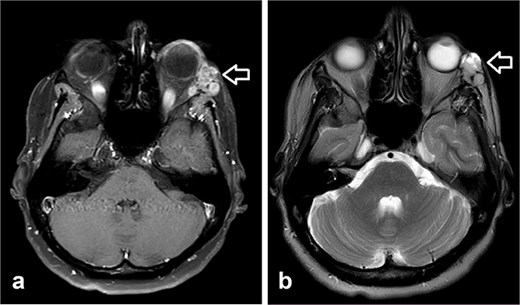

A 27-year-old female patient with no significant medical history presented with a painless lump over the lateral canthus of her left eye. Over several months, the swelling enlarged, causing intermittent, localized pain without numbness, facial palsy, or visual changes. Examination revealed a well-oriented patient with normal cranial nerves and a non-tender left lateral eye swelling. CT scan showed a 3 × 3 × 2.7 cm soft tissue mass with destruction of the lateral orbital wall, while the optic nerve and neck lymph nodes were normal. Biopsy confirmed adenoid cystic carcinoma (ACC).

The patient underwent left orbital transcanthal craniotomy and orbitotomy with resection of the left retro-bulbar tumor. Left neck dissection was conducted with excision of lymph nodes for staging. Assessment of the margin was not performed due to the fragmented nature of the bone, so the patient underwent adjuvant radiotherapy (Fig. 1).

(a) CT scan showed left orbital mass with both solid enhancing and cystic components. The epicenter of the mass appears to be in the left lacrimal gland. (b) MRI postoperative that showed complete tumor excision.